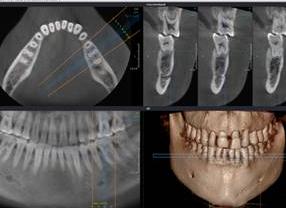

Компьютерная томография (КТ) — это диагностический метод, позволяющий получить детальную картину состояния всей ротовой полости. В результате специалист получает 3D-изображение челюсти пациента. Исследование проводится при помощи специального аппарата, который носит название «дентальный компьютерный томограф».

В результате исследования можно получить трехмерное изображение челюсти. По нему врач определяет аномалии, выявляет проблемы, определяет, насколько качественно было проведено протезирование и многое другое.

Ранее для того, чтобы увидеть в зубной полости то, что скрыто внутри, использовалось рентгенологическое обследование. Компьютерная томография — это тот же рентген, только трехмерный. То есть на выходе получаются не плоские малоинформативные снимки, а настоящая компьютерная модель зубной челюсти со всеми ее патологиями. Стоматолог получает возможность, образно говоря, повертеть челюсть пациента в руках, рассмотреть ее послойно и таким образом определить глубину проблемы.

• получаемый 3D снимок дает развернутую информацию о состоянии зубного ряда, скрытых проблемах с челюстью, ширине кости;

Компьютерная томография зубов представляет собой исследование челюсти, которое проводится при помощи такого специального аппарата, как томограф. Благодаря ему за одно сканирование можно получить подробную информацию о том, в каком состоянии находятся зубы пациента. В результате исследования врач получает трехмерный снимок зуба, на котором можно рассмотреть челюсть пациента в полном объеме. Это позволяет поставить гораздо быстрее правильный диагноз и составить необходимый план лечения. КТ зубов предоставляет широкие возможности для стоматолога и удобство для пациента.

В результате томографии получается 3 D снимок, который в электронном виде записывают на DVD -диск или флеш-карту. Это позволяет провести комплексное лечение различными специалистами. Компьютерная томография зубов обследует не только челюсть пациента, но и носовую перегородку, верхнечелюстные пазухи, среднее и внутреннее ухо, височную кость и наружный слуховой проход.

• Это эффективно! Позволяет врачу выбирать точные области сканирования и безошибочно назначать эффективное лечение, учитывая все особенности пациента. Стандартное изображение челюсти размерами 8 см в диаметре и высотой 8 см используется для планирования имплантаций, эндодонтического лечения и хирургических вмешательств; Расширенное сканирование с изображением размерами в 14 см диаметром и 8 см высотой применяется для обследования челюстных суставов и дыхательных путей.

• Это наглядно! Данные, полученные с помощью КТ, визуализируются в различных проекциях и под любыми углами зрения. Они отражаются в компьютерной программе в виде ярких 3D моделей. Врач может обращаться к любому слою снимка и наглядно демонстрировать пациенту все его проблемные места и результаты лечения. 3D-сканирование на 360 градусов охватывает оральные и лицевые области.

В последние десятилетия технология компьютерной томограммы неуклонно развивается, в результате чего даже очень современным устройствам не нужно перемещать механические части вокруг пациента. 3Д-компьютерная томография зубов создает несколько изображений, которые обычно отображаются бок о бок и один под другим, так что пространственное расположение структур можно изучать с уровня на уровень.